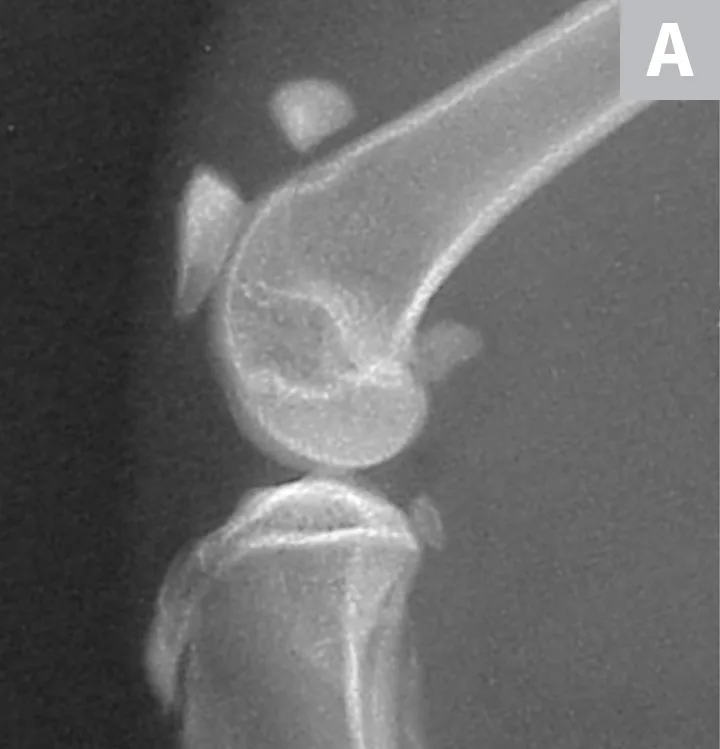

The patient received buprenorphine (15 µg/kg IV) for analgesia, followed by an induction with alfaxalone (0.5 mg/kg IV) and general anesthesia with isoflurane to facilitate dental and orthopedic radiography. Dental radiographs revealed persistent deciduous teeth and impacted permanent teeth. Lateral and craniocaudal pelvic limb radiographs revealed a displaced left patellar fracture and a nondisplaced right patellar fracture (Figure 2).

Lateral radiographs of the left (A) and right (B) stifles show a complete, displaced left patellar fracture and a nondisplaced right patellar fracture, respectively.